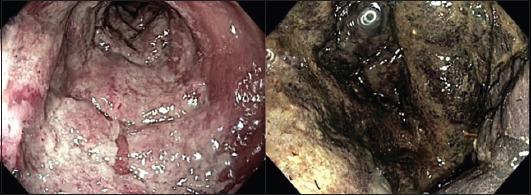

METHODS

In this single-center retrospective analysis, IC was scored according to endoscopy as: grade 1 (hyperemia, <1 cm erosions and non-confluent ulcers); grade 2 (>1 cm superficial, partially confluent ulcers); and grade 3 (deep or diffuse ulcers or necrosis). Then, IC was grouped into low- (grade 1) and high-grade (grades 2 and 3). Significant (P≤0.1) independent factor of severe IC at univariate analysis were entered into multivariate analysis and considered significant at P<0.05.

在这项单中心回顾性分析中,IC根据内镜检查分为:1级(充血、<1 cm糜烂及非融合性溃疡);2级(>1 cm浅表、部分融合性溃疡);3级(深部或弥漫性溃疡或坏死)。然后,IC被分为低级别(1级)和高级别(2级和3级)。单因素分析中与严重IC显著相关(P≤0.1)的独立因素纳入多因素分析,P<0.05时被视为具有显著性。